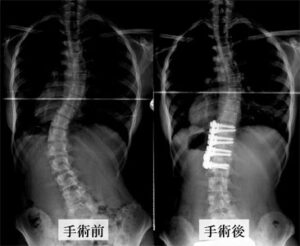

手術方法は大きく分けて前方法(図3)と後方法(図4)の二つに分けられます。

(1)前方法 (図3、図4参照)

前方法は背骨の前方成分、すなわち椎体や椎間板を実際に触って矯正する方法です。

麻酔をかけた後、手術台の上で横向きに寝ていただきます。そして、肋骨に沿って皮膚を切開し、肋骨を1本切除して椎体や椎間板に側方よりアプローチします。そして、矯正予定範囲の椎間板を切除し、そこに外した肋骨を移植して、椎体にスクリューを1-2本入れてロッドで矯正を行います。

(2)後方法 (図3、図4参照)

背中に縦の皮切を加えて、背骨から筋肉を剥がして棘突起、椎弓、横突起といった背骨の後方組織を露出します。

矯正に使用する機械は主に椎弓根スクリューとロッドを使用します。時によってはフックやワイヤーも使用します。(図5)

椎弓根にスクリューを設置し、そこにロッドを連結させて様々なテクニックを用いてカーブを矯正していきます。(図6)